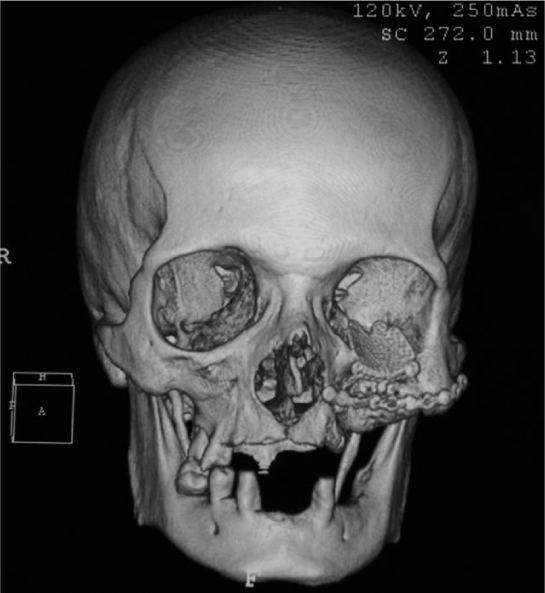

On aspiration biopsy was obtained by easily obtaining a light brown coloring liquid with blood residues. Under local anesthesia, incisional biopsy was performed for histopathological study, which later reported the antralpseudocyst, and its surgical enucleation was scheduled. Complementary imaging studies were carried out, which showed a radiolucent lesion in his tomographic image that occupies and destroys the left side of the jaw, including the floor of the orbit (Figure 2). A stereolithographic model was developed for the planning of the procedure (Figure 3).

It is important to perform a correct diagnosis of the antral pseudocyst because it usually does not require treatment for its size less and does not inflate adjacent tissues [10], in counter position to some of the differential diagnoses that require surgical treatment such as mucocele [11], as well as differentiate it of the majority of odontogenic cysts and tumors requiring enucleation or resections with injury-free margins [12]. In the present case the behavior of the cyst was completely different from that described in the literature as it infiltrated and caused destruction of the floor of the orbit and left jaw.